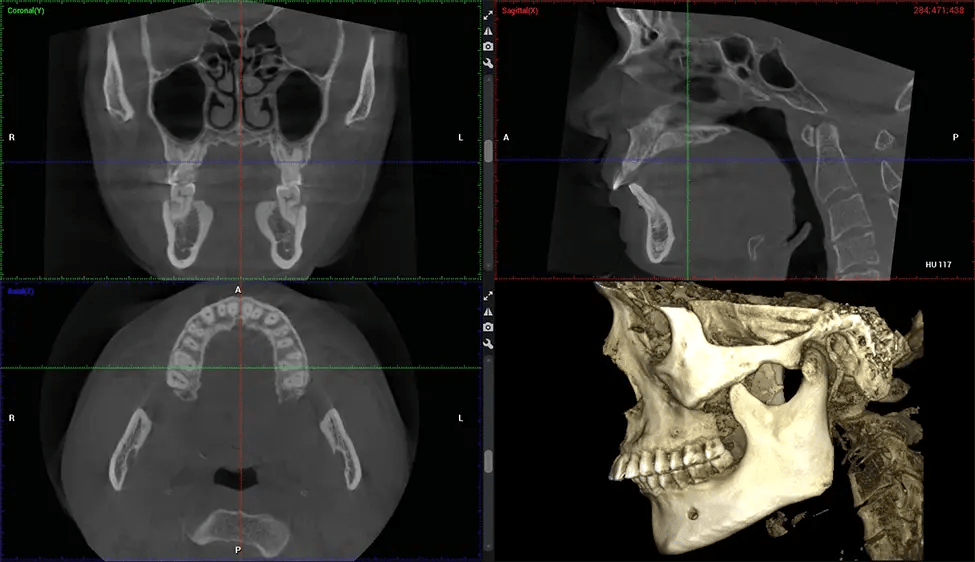

Cráneo completo hasta C7 de la columna vertebral

Planmeca Viso G7 CBCT La tomografía computarizada de haz cónico (CBCT) está diseñada para superar las exigencias de los líderes de la industria, los especialistas y las grandes instituciones. Cuenta con un sensor de gran tamaño (25 × 30 cm) con cuatro cámaras integradas. Puede capturar tamaños de volumen ilimitados, desde ø3×3 cm hasta ø30x30cm, capturando el casquete escutelario a través de C7 en la columna cervical. Planmeca Viso G7 ofrece el escaneo de volumen único más grande de la industria de ø30×19 cm. Está preparado para manejar modalidades de imágenes avanzadas como la tecnología Planmeca ProFace® y Planmeca 4D™ Jaw Motion. El soporte occipital para la cabeza permite una visión sin obstáculos del tejido facial.

Planmeca es el único fabricante clínicamente probado que reduce drásticamente la radiación del paciente sin sacrificar la calidad de la imagen. Planmeca Ultra Low Dose™ logra una reducción promedio de la dosis del 77% sin una reducción estadística en la calidad de la imagen, lo que permite a los médicos incorporar imágenes 3D en protocolos de rutina con una radiación efectiva al paciente a menudo inferior a la de las imágenes intraorales 2D.. Esto aumenta la atención al paciente, permite a los médicos diagnosticar más odontología y, a menudo, antes en la progresión de la enfermedad, que con imágenes 2D solas.